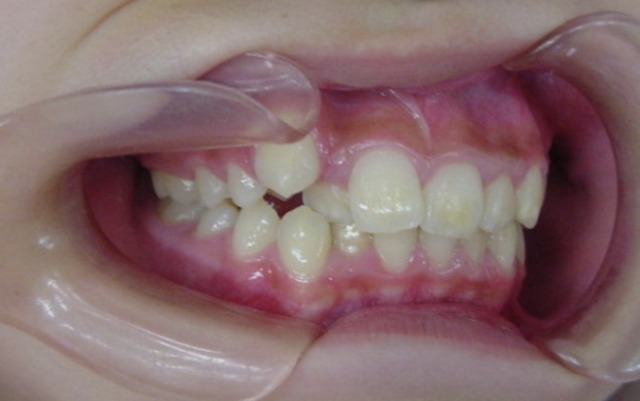

Before